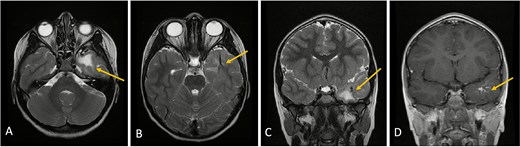

MRI with and without gadolinium contrast identified a vascular lesion consistent with a DVA in the left anterior temporal lobe. This showed typical caput medusae venous morphology. Adjacent white matter T2/FLAIR hyperintensities were present without diffusion restriction or blooming on gradient-echo sequences. No abnormal contrast enhancement was noted, and major venous sinuses were patent (Figs 1 and 2).

Axial lower cut (A)/axial higher cut (B)/coronal (C) T2-weighted MRI of the brain shows a prominent area of T2 hyperintensity (arrow) in the white matter of the left anterior temporal lobe, adjacent to the DVA. The DVA itself is clearly delineated on the contrasted sequence (D) and its draining veins contribute to the local anatomy (arrow). (E) Axial FLAIR (fluid-attenuated inversion recovery) highlights the abnormal hyperintensity in the left anterior temporal lobe white matter (arrow), suppressing the cerebrospinal fluid signal and making the white matter changes more conspicuous. This represents chronic changes such as gliosis or edema.

Clinical and radiological follow-up was advised. Serial MRIs at two and four months demonstrated no change in venous morphology or white matter signal. The patient’s clinical course remained uneventful, with no neurological deficits noted (Fig. 3).

Axial lower cut (A)/axial higher cut (B)/coronal (C) T2-weighted MRI of the brain shows stable findings of a prominent area of T2 hyperintensity in the white matter of the left anterior temporal lobe, adjacent to the known DVA (arrow), which is clearly delineated on the contrasted sequence (D).